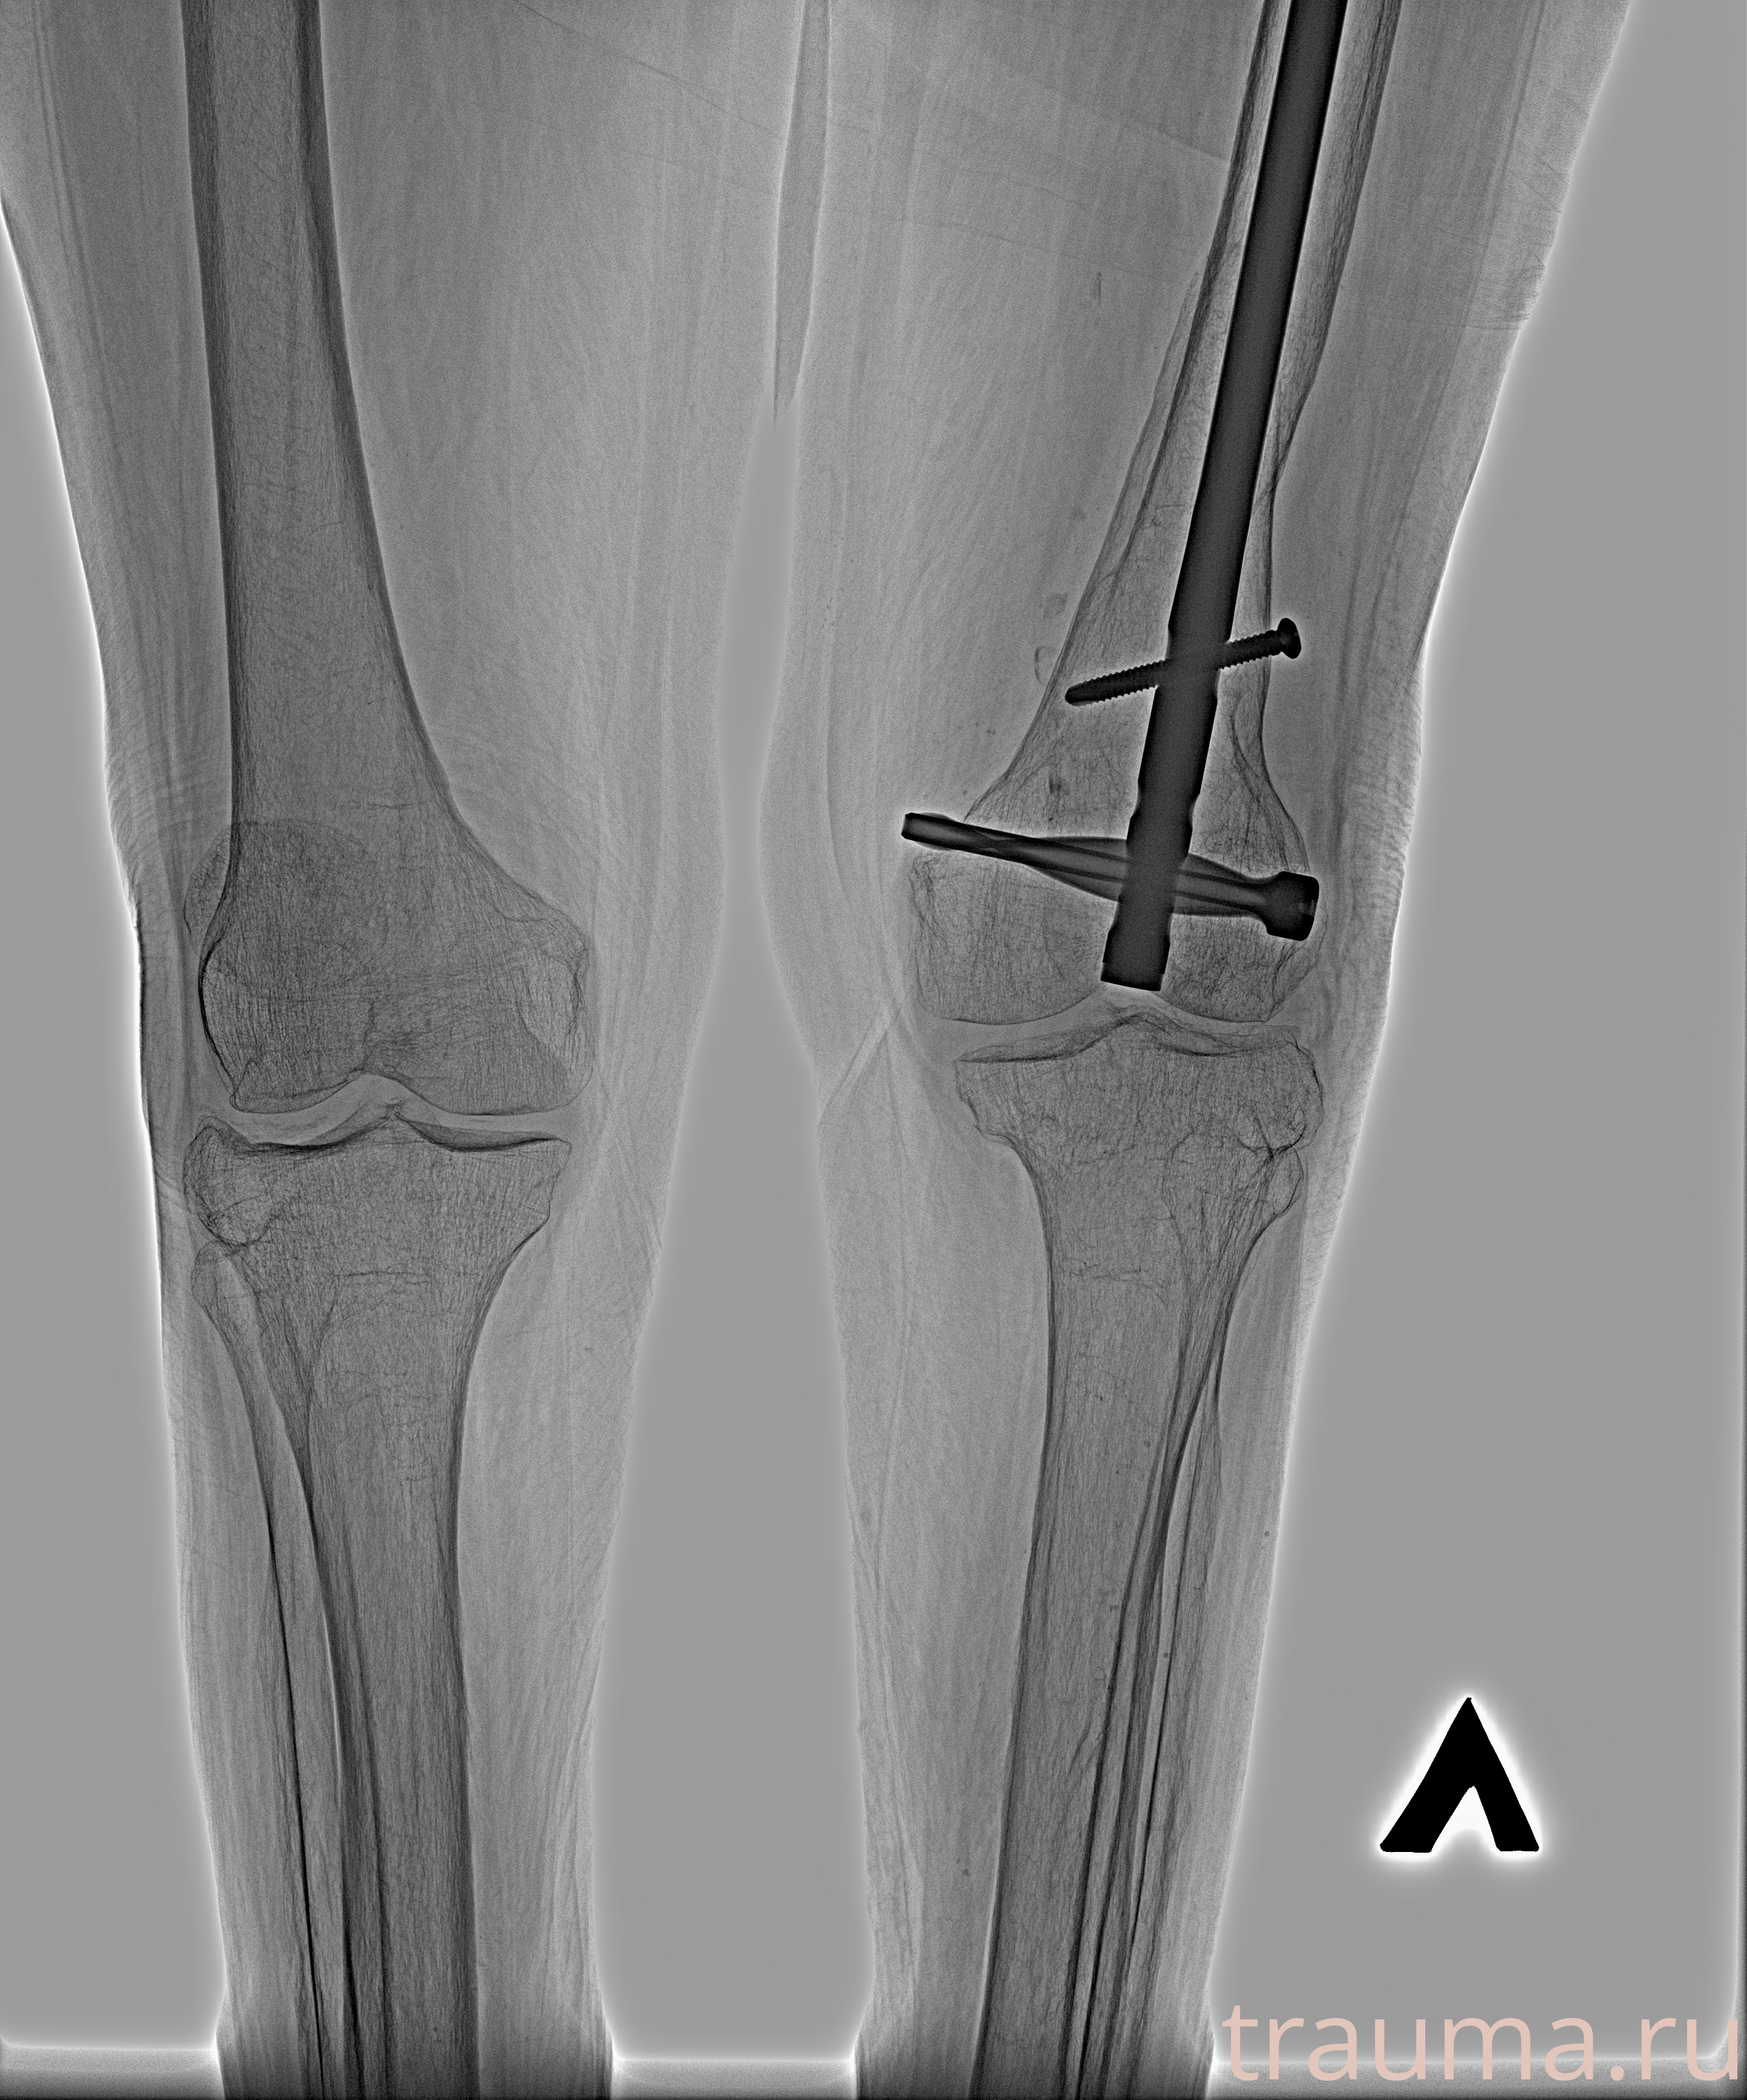

Перелом 3-5 ребер слева